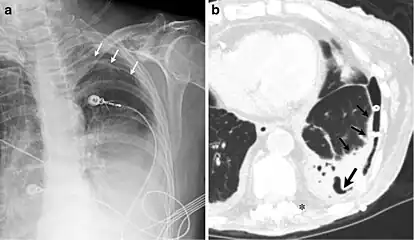

A fibrothorax can typically be diagnosed by taking an appropriate medical history in combination with the use of appropriate imaging techniques such as a plain chest X-ray or CT scan.[3] These imaging techniques can detect fibrothorax and pleural thickening that surround the lungs.[7] The presence of a thickened peel with or without calcification are common features of fibrothorax when imaged.[3] CT scans can more readily differentiate whether pleural thickening is due to extra fat deposition or true pleural thickening than X-rays.[3]

If a fibrothorax is severe, the thickening may restrict the lung on the affected side causing a loss of lung volume.[7] Additionally, the mediastinum may be physically shifted toward the affected side.[3] A reduction in the size of one side of the chest (hemithorax) on an X-ray or CT scan of the chest suggests chronic scarring.[6] Signs of the underlying disease causing the fibrothorax are also occasionally seen on the X-ray.[6] A CT scan may show features similar to those seen on a plain X-ray.[7] Lung function testing typically demonstrates findings consistent with restrictive lung disease.[6]

CXR of an individual affected by fibrothorax (consequence of tuberculosis)